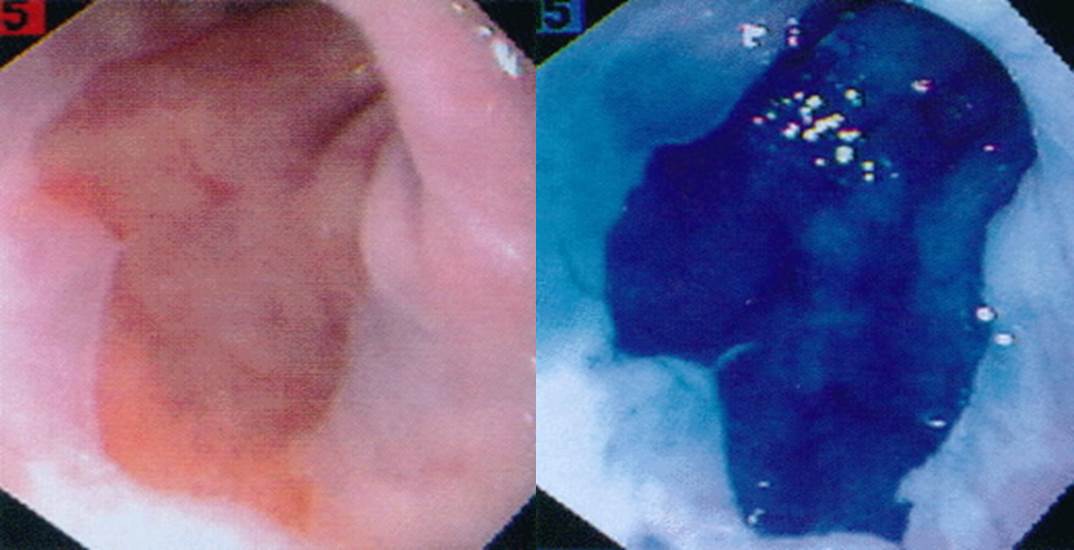

ÀÎÅͳݿ¡¼ °¡Á®¿Â »çÁø. Barrett esophagus¿¡¼ methylene blue¸¦ »ç¿ëÇϸé ÀÌ·¸°Ô uptake°¡ µÈ´Ù°í ÇÕ´Ï´Ù. ½ÇÁ¦·Î ÇØ º¸¸é ÀÌ·¸°Ô °ÇÏ°Ô ¿°»öµÇÁö´Â ¾ÊÁö¸¸...

Metaplastic gastritis¿¡¼ methylene blue¸¦ »ç¿ëÇÏ¿© »çÁøÀ» Âï¾ú½À´Ï´Ù. ¸Ç´«À¸·Îµµ Àß º¸ÀÌ´Â °ÍÀ» ¿°»öÇØº¸¸é ´õ Àß º¸ÀÔ´Ï´Ù. °á±¹ ÀÓ»óÀû ÀÇÀǰ¡ ¾ø´Ù´Â ¶æÀÔ´Ï´Ù. ÇÑ 10³â Àü¿¡ ÀÌ »çÁøÀ» ¸¶Áö¸·À¸·Î ´õ ÀÌ»ó methylene blue¸¦ »ç¿ëÇÏÁö ¾Ê°í ÀÖ½À´Ï´Ù.